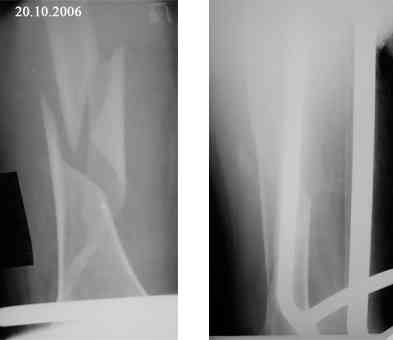

Представляю вашему вниманию снимки в динамике

Женщина 66 лет 15.10.2006 получила закрытый окольчатый перелом правой бедренной кости в с\з-н\з со смещением отломков. 17.10.2006 доставлена в травм.отделение (2-е суток лежала одна дома). При поступлении наложено скелетное вытяжение за бугристость большеберцовой кости - груз 5 кг, затем увеличен до 7 кг. Схематические рисунки контрольных Р-грамм прилагаются (прошу прощения за отсутствие Р-грамм, постараюсь "донести").В связи с отсутствием материальных средств и "удовлетворительным" положением отломков решено было скелетное вытяжение оставить как окончательный метод лечения. На 20.11.2006 отека правого бедра нет, пальпаторно умеренная болезненность в месте перелома, крепитации отломков нет (и по-видимому не было изначально),подвижность в месте перелома сохранена, но не выражена. Двигательных, чувствительных и трофических расстройств правой нижней конености нет. Уважаемые коллеги! Какова дальнейшая тактика в случае вероятной интерпозиции тканей? Больная "кровавое" оперативное лечение не "потянет" материально. Даст ли в данном случае что-то АВФ закрыто?